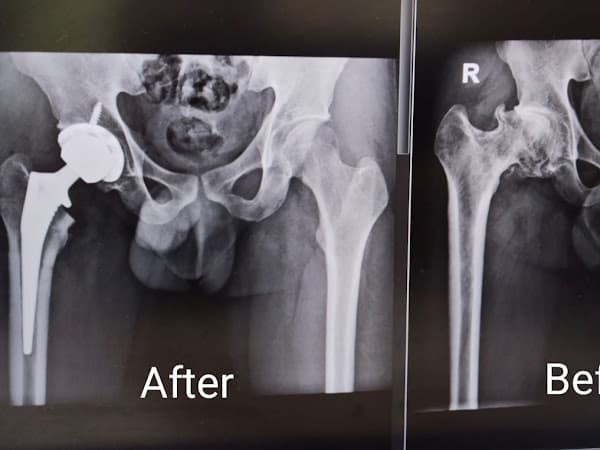

Hi everyone, I'm a patient of Dr. Chan Chee Ken at Mahkota Hospital. It's now one week post Hip Implant Replacement for me. I want to share my truly remarkable experience with him. Dr. Chan Chee Ken is a specialist in Joint procedures, like total hip replacements, and his expertise truly shines through. The change in my condition is just incredible. You can see it for yourself in the before and after X-ray photos I uploaded – the results speak for themselves. If you're a mathematician or physicist. You'll really appreciate how Dr. Chan works. He's like a "Mathematician in The World of Medicine." Everything he does is measured and planned with extreme precision and Mathematical accuracy. This just gives you complete confidence in his expertise and carefulness. What's even more mind-blowing is that I was able to walk with just a little assistance (using a walking stick) within one day after the surgery! That's an unbelievably fast and great recovery. Beyond being a fantastic surgeon, Dr. Chan Chee Ken also has great integrity. He's very approachable and really connects with his patients, always making sure he's there for every step of our recovery and progress. This kind of personal care and dedication is truly rare and very comforting. I strongly recommend Dr. Chan Chee Ken to anyone needing orthopedic care, especially for Total Hip Replacement or other complicated Joint surgeries. His unique skills, careful approach, and wonderful patient care truly make a huge difference.